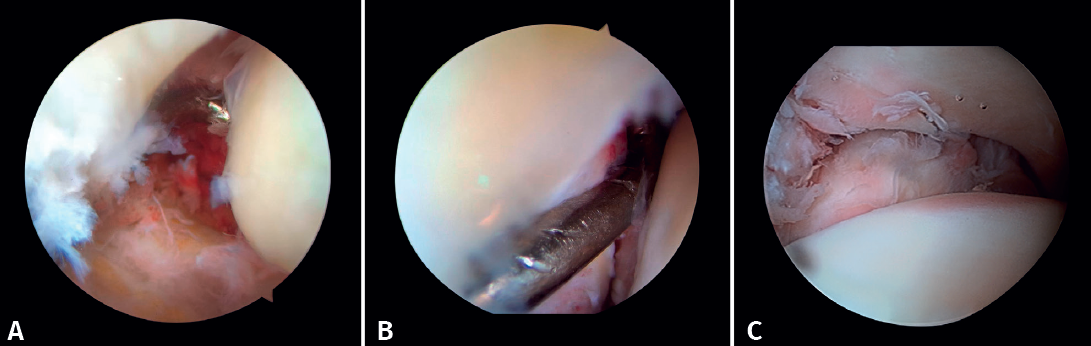

Arthroscopy assists ORIF in evaluating the congruence of the joint surface. It is especially useful for reduction of the medial malleolus. The malreduction rate in medial malleolus fractures is 22.2-32.6%(15,16). Initial arthroscopy allows us to determine whether tibial malleolus reduction can be performed in an open or closed manner. In cases with significant displacement, open synthesis is chosen, always maintaining arthroscopic control during the procedure to ensure precise reduction and avoid rotation of the distal fragment (Figure 4).

- Diagnosis of syndesmotic instability. Arthroscopy allows assessment of the integrity of the syndesmosis and the MCS on the radiograph and CT scan, especially in SER II and IV fractures. It has been shown that radiographic assessment is not always predictive of the syndesmotic lesion. In addition, arthroscopy ensures its anatomical reduction. Takao found that 87% (33/38) of the ankles with fractures had syndesmosis lesions detected by arthroscopy(20).

Arthroscopy allows both direct visualization and dynamic assessment of the syndesmosis(21,22).

- Being able to visualize the malleolar incisura together with radioscopic control allows us to ensure correct positioning of the incisura fibularis, especially in patients with unstable injuries where there is a risk of malreduction due to shortening or rotation of the fibula(5,24).

- Arthroscopy can help avoid overcorrection of the syndesmosis, which is highly arthrogenic(5,24)(Figure 6).

Xie showed that stabilization of the syndesmosis with a dynamic fixation system offers equivalent functional results and fewer complications compared to screw fixation(28). AAORIF allows the evaluation of joint congruency after anatomical reduction of both the posterior and anterior syndesmosis. It also allows assessment of the overcorrection that can result from over-compression of the tibiofibular mortise, which has been shown to be highly arthrogenic(29). During reduction of the syndesmosis, help is provided by a palpation probe which we should be able to insert once the syndesmosis has been fixed.